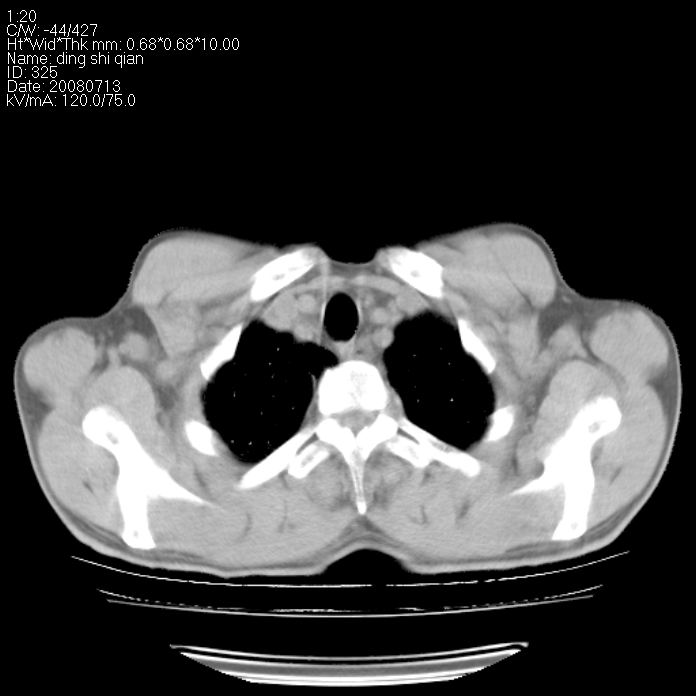

标题: CT14654:男 50岁 近来胸痛 [打印本页]

标题: CT14654:男 50岁 近来胸痛

右侧上肺块状软组织影,浅分叶,边缘毛刺证,与胸膜粘连,考虑:周围性肺癌

右肺上叶周围型肺癌可能性大。

右侧上肺块状软组织影,浅分叶,边缘毛刺证,与胸膜粘连,考虑:周围性肺癌!支持!

典型右肺周围型肺癌

右肺上叶周围型肺癌。